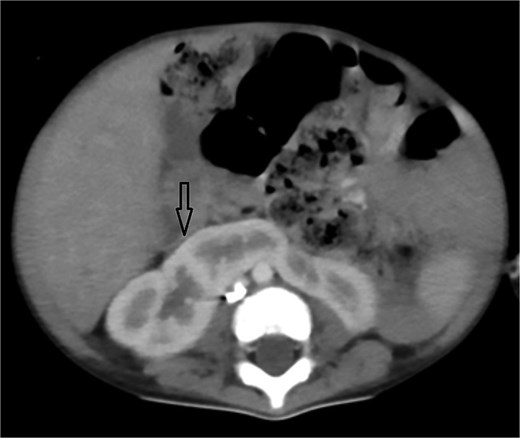

Axial CT angiogram in lung window demonstrating right lower-lobe consolidation and volume loss with mediastinal shift, consistent with pneumonia and compression by the pseudoaneurysm.

Urgent transthoracic echocardiography demonstrated a large echodense mass in the right hemithorax, compression of the right atrium and reduced flow through the right-sided shunt. Computed tomography angiography (CTA) confirmed a massive saccular pseudoaneurysm (≈8 × 7 × 6 cm) arising from the anastomosis between the right subclavian artery and the mBTTS graft, completely thrombosed without active contrast extravasation (Fig. 1). There was complete thrombotic occlusion of the right pulmonary artery, right lung collapse due to extrinsic compression and right lower-lobe consolidation consistent with pneumonia (Fig. 2). CTA also revealed left isomerism with central liver and polysplenism (Fig. 3) and a horseshoe kidney (Fig. 4), suggesting a previously unrecognized polymalformative syndrome.